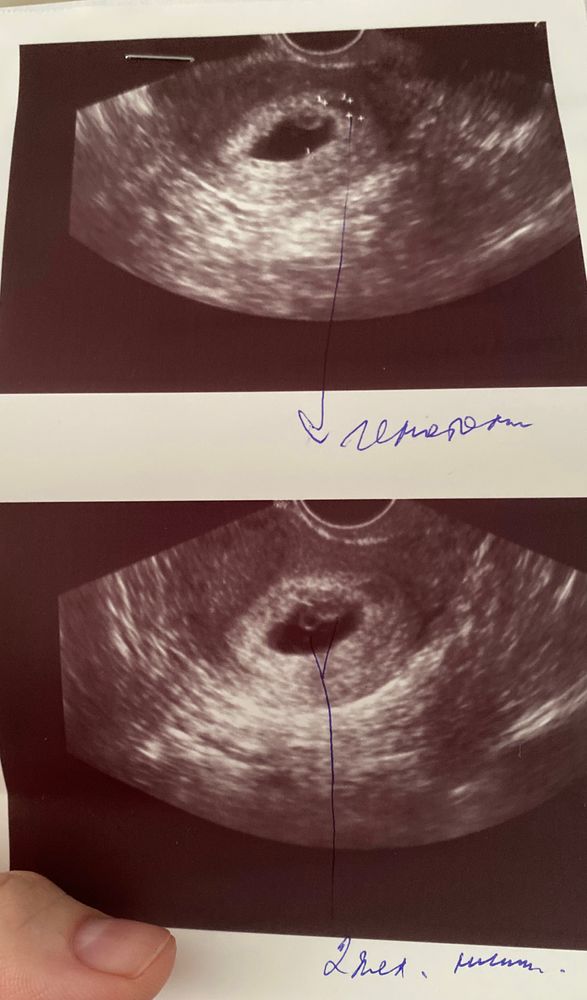

На повторном узи (6 недель 4 дня) обнаружили 2 желточных мешочка. Эмбрион с сердцебиением нашли пока один только. Врач долго смотрела и сомневалась, желточный ли мешочек это или начала развиваться плацента. Подскажите, было ли у кого такое, что под вопросом была многоплодная беременность, но потом она не подтвердилась? И вообще реально ли плаценту на узи спутать с желточным мешочком? Или может быть просто 2 желточных мешка, но один эмбрион?

На втором фото чётко один эмбрион и желточный мешок.Плацента с 16 недель,до этого срока -хорион.И то,его неделям к 10 только видят